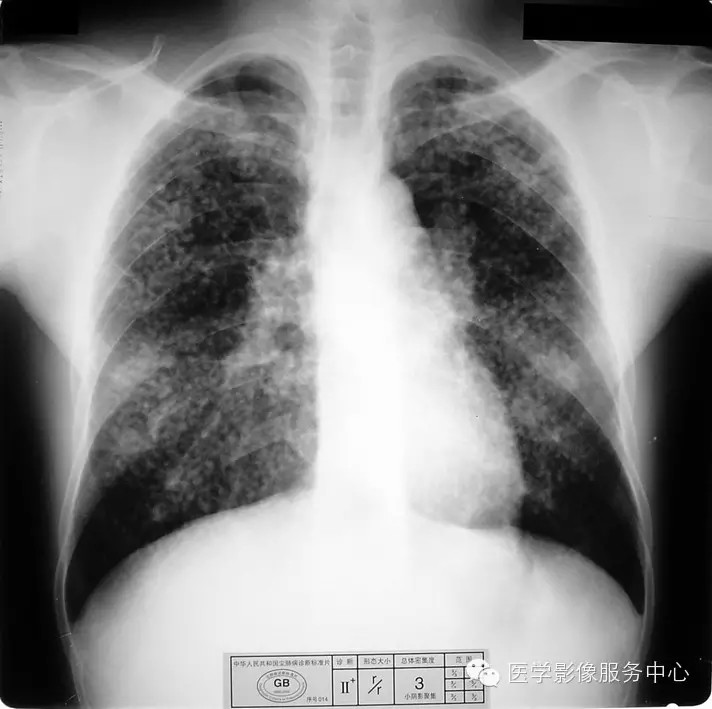

b)Ⅱ :有总体密集度3级的小阴影,分布范围超过4个肺区;或有小阴影聚集;或有大阴影,但尚不够诊断为Ⅲ者。